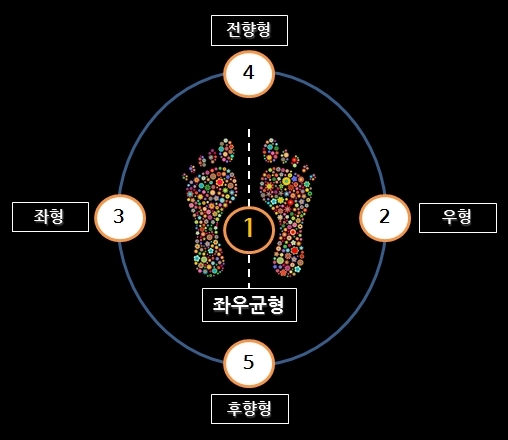

또 제자리걸음을 이용한 자가진단법도 있는데요. 눈을 감고 팔을 크게 흔들면서 다리를 높게 올리는 제자리걸음을 50회 반복합니다. 그리고 눈을 뜨고 위치를 확인했을 때, 처음 위치 그대로라면 굉장히 바른 체형이라고 볼 수 있습니다. 하지만 처음 있는 곳에서 벗어났다면, 그 방향으로 골반이 틀어진 것인데요.

골반이 앞으로 기울어진 전향형, 뒤로 기울어진 후향형과 왼쪽 골반과 어깨가 처져있는 좌형, 반대인 우형으로 나눌 수 있습니다.

추가로 몸의 방향이 처음(자신이 보고 있던 방향)에서 왼쪽으로 돌아갔다면 좌향형, 반대면 우향형으로 나눌 수 있는데요. 골반이 왼쪽으로 돌아가 있는 상태인 좌향형은 상체가 왼쪽으로 돌아가 있고 오른쪽 어깨가 앞으로 나와 있으며, 우향형은 그 반대라고 합니다.